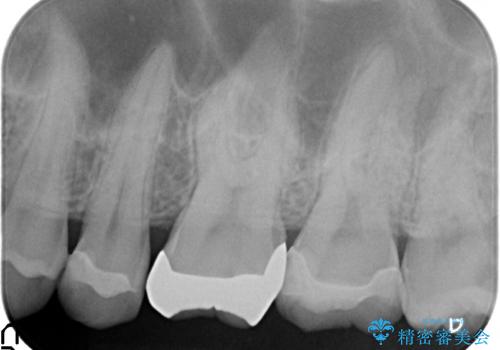

- 健診で虫歯があると言われたので診て欲しいといらっしゃった方の症例です。

左上5、6、7番目の歯に虫歯を認めたため、左上5、7はセラミックインレーによる修復を行いました。

左上6に関しては患者様の希望でパラジウムインレーによる修復を行いました。